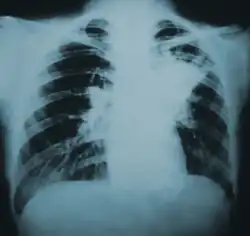

![]() | |

| Lung infiltration in blastomycosis. | |